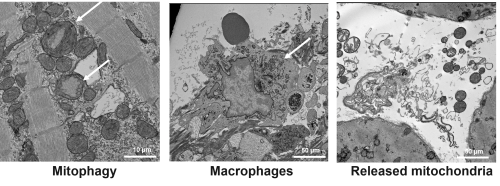

Dysfunctional mitochondria of cardiomyocytes contribute to cardiac remodeling and left ventricular dysfunction in repAMI. Hallmarks are perturbations in substrate flux towards mitochondria, substrate utilization, and mitochondrial oxidative metabolism. Defective mitochondrial clearance in cardiomyocytes results in the accumulation of waste mitochondria and cell death. The underlying mechanisms are not fully understood, but suggest a reciprocal signaling between macrophages and cardiomyocytes affecting removal of damaged mitochondria.

- Mechanisms and regulation of cardiomyocyte mitochondrial removal

Mitochondrial clearance in human tissue